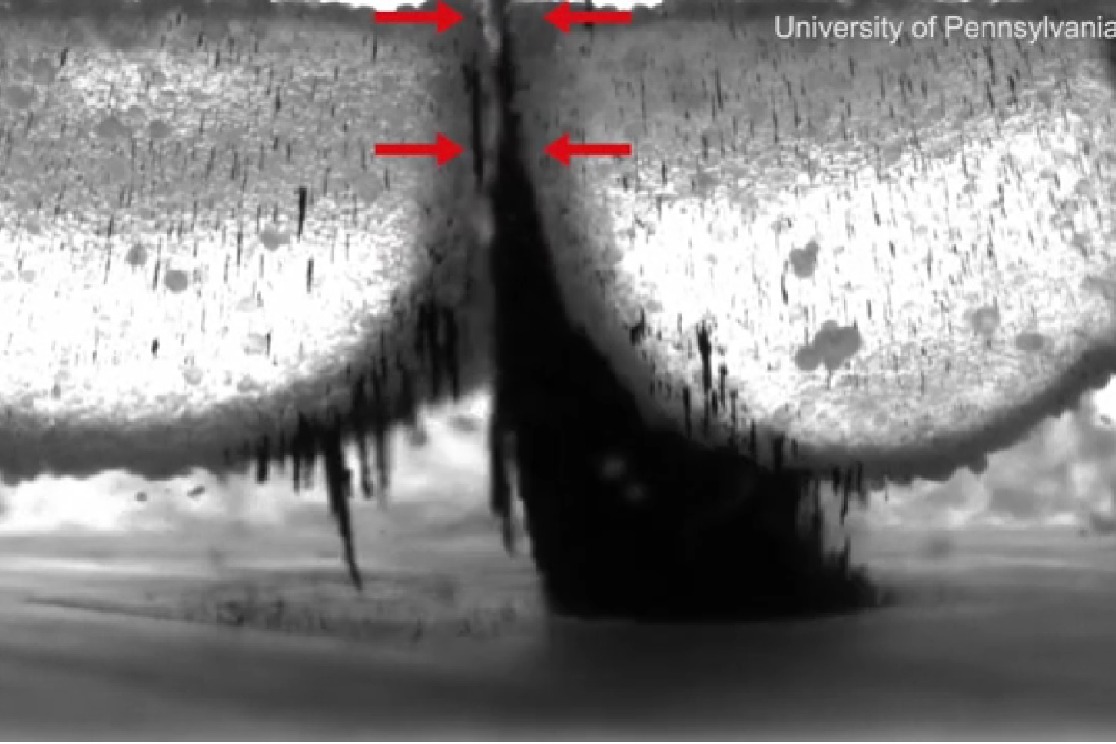

ఉదయం నిద్ర లేవగానే చేసే పని పళ్లు తోముకోవడం. ఈ పని సరిగా చేయకపోతే ఎన్నో ఆరోగ్య సమస్యలను ఎదుర్కొవాల్సి వస్తుంది. ఇందుకోసం సరిగా బ్రషింగ్ చేయడం అవసరం. చాలా మందిలో పళ్లు వివిధ ఆకృతుల్లో అమరి ఉంటాయి. అందువల్ల చాలా వరకు టూత్ బ్రష్ లు మన పళ్లను పూర్తిగా శుభ్రం చేయలేవు. ఈ పనిని సులభతరం చేసేందుకు చాలాకాలంగా ప్రయత్నాలు సాగుతున్నాయి. ఈ క్రమంలోనే పెన్సిల్వేనియా పరిశోధకులు సూక్ష్మస్థాయి ఐరన్ ఆక్సైడ్ కణాలతో ఆకారాన్ని మార్చుకునే రోబోలను తయారు చేశారు. వాటిని ఆయస్కాంతాల సాయంతో నియంత్రిస్తారు.

ఒకదానికి మరొకటి అతుక్కునే ఐరన్ ఆక్సైడ్ నానో కణాలు.. మన దంతాల ఆకృతి, మధ్యలో ఉండే సందులకు అనుగుణంగా తమ ఆకారాన్ని మార్చుకుంటాయి. అతి సన్నని బ్రెసిల్స్ (బ్రష్ లోని పోగులు)గా కూడా మారి పళ్ల సందుల్లోకి వెళ్లి శుభ్రం చేస్తాయి. వేర్వేరు ఆకృతుల్లోకి మారిపోతూ పళ్లకు పట్టిన గారను కూడా శుభ్రం చేస్తాయి.